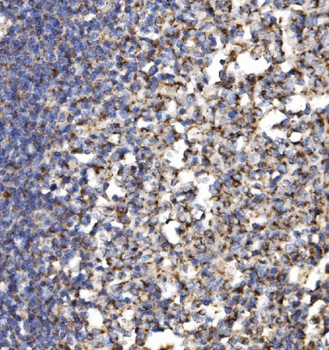

100 μl, 50 μl, 200 μl - ATF4 Recombinant Rabbit Monoclonal Antibody [orb704304]Featured

FC, ICC, IF, IHC-Fr, IHC-P, WB

Human

Mouse

Rabbit

Recombinant

Unconjugated

50 μl, 100 μl - MARK3 Recombinant Rabbit Monoclonal Antibody [orb704310]Featured